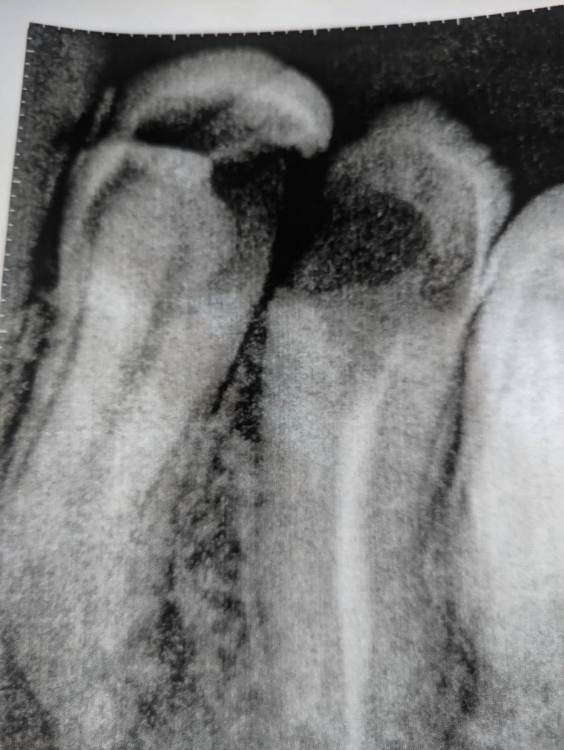

sergiokrut Опубликовано 19 января, 2022 Поделиться Опубликовано 19 января, 2022 Здравствуйте. Один старый зуб с фото по центру удалили. В левом на фото ( около клыка сверху) была дырка и он недавно треснул (не полностью, а половина видимая до десны почти. Был у стоматолога - терапевта, говорит ничего не может сделать. Доверия нет и терапевт может ошибаться.Возможно корень целый еще и можно наростить, имплант, штифт или еще что-то сделать и спасти зуб? Ссылка на комментарий